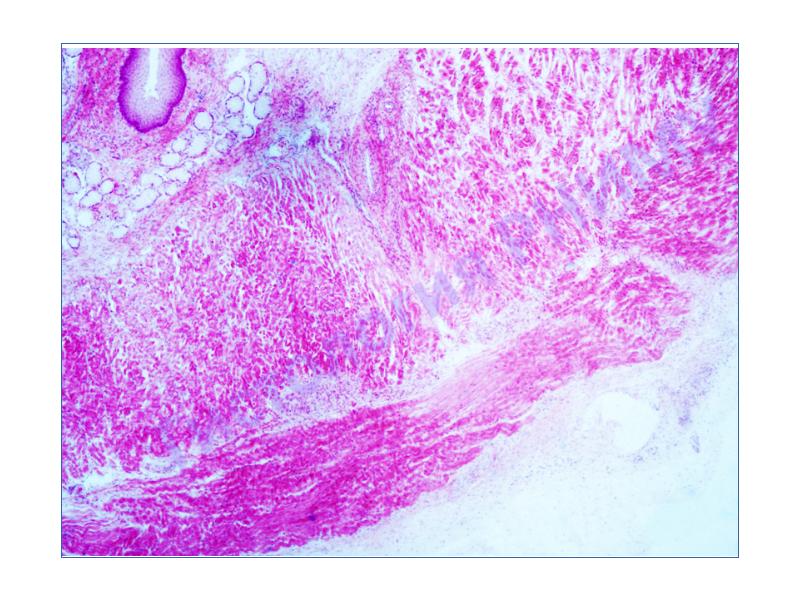

Гистологические снимки полипов фундальных желез желудка